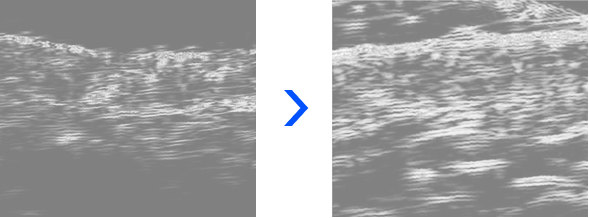

Ultrasound Analysis of Changes in Skin Cell Density and Structure

Over time, skin density and thickness gradually increased, collagen density and dermal structure strengthened, and overall skin elasticity improved